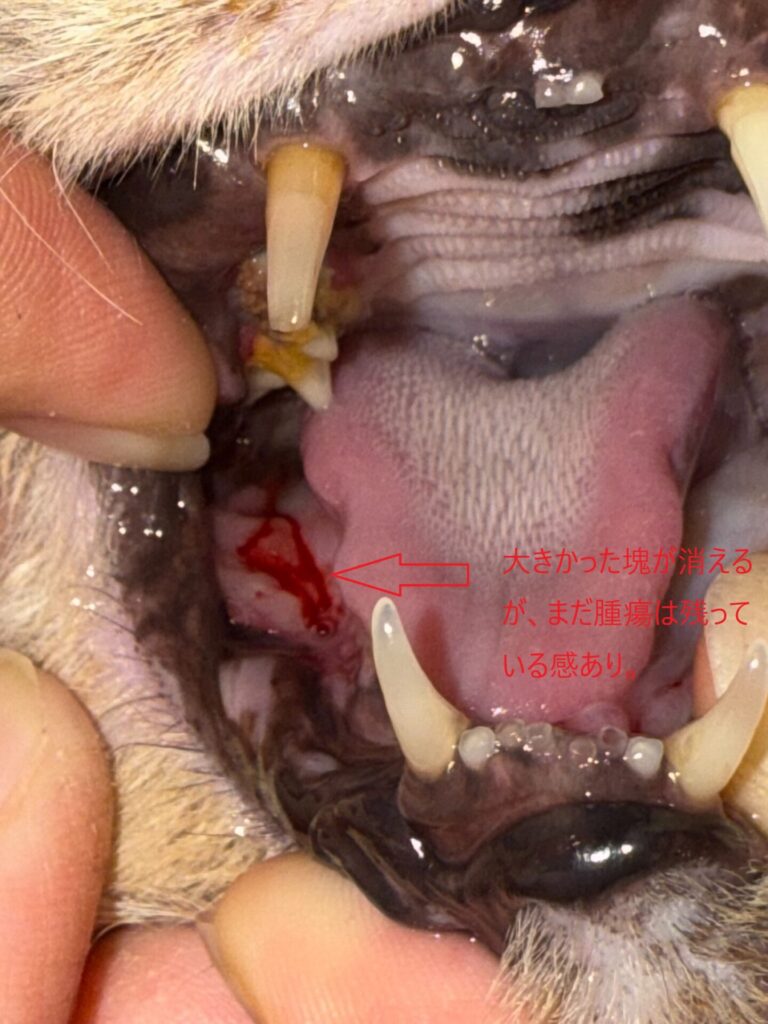

【今日、2025、8,27の右奥写真】 ⇩

【上のアップ】 ⇩

あの大きかった癌塊は消える。

しかし、まだ、ガン組織はもう少し残存しているようで、周囲からの出血はあるも、

血液は鮮血色で快方に向かっているのでは?と思われる。

化膿とかの汚染もなく口内環境は良い。